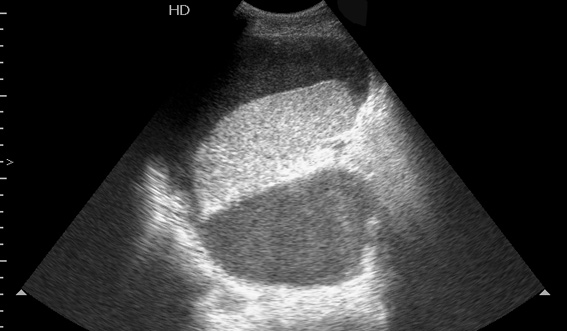

Мужчина средних лет, страдающий хроническим панкреатитом.

Температура 38-39 град, симптомы интоксикации, невыраженная боль в левом боку.

При УЗИ в области ворот селезенки/хвоста панкреас определяется жидкостное образование, переходящее в поддиафрагмальное пространство и заполненное акустически непрозрачной, мутной жидкостью.

Сонограмма селезенки. Продольное сканирование из левого бокового доступа.

Образование задренировано, получена гнойная жидкость с геморрагическим компонентом.